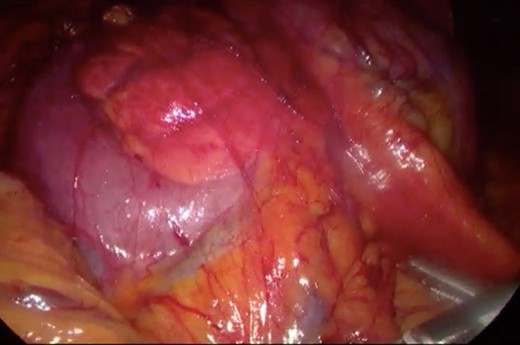

Initially, conservative management was adopted with some improvement of patient’s nutrition condition. However, as symptoms persisted, surgical treatment was recommended. Our surgical approach was a laparoscopic duodenojejunostomy with a latero-lateral stapled anastomosis between jejunum (30 cm from Treitz’s angle) and the second portion of the duodenum (Figs 5–9). The patient recovered with no pain but with a delay in diet acceptance. An upper GI contrast study was performed on the fifth post-operative day revealing a distended stomach with gastric emptying delay, but with unobstructed anastomosis, therefore without stenosis or leaks (Fig. 10). She was discharged home after 8 days with liquid diet and digestive transit restored. After 3 months of follow-up, the patient gained some weight and remained asymptomatic.

Surgery—laparoscopic visualization of the second and third portion of duodenum.